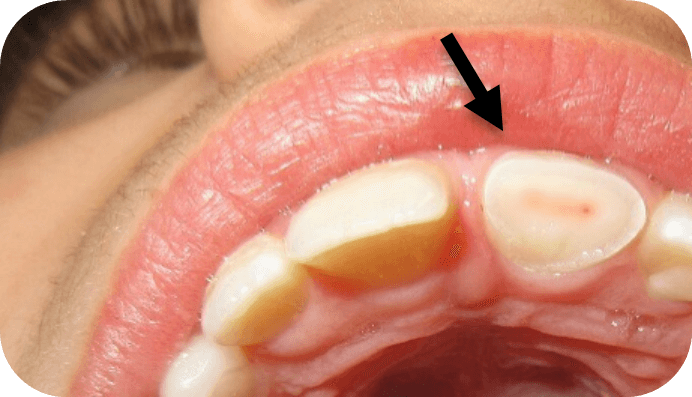

- Recent Trauma or Injury: temporary loss of response due to inflammation/reduced blood flow.

- Recent Trauma or Injury: may cause hypersensitivity and prolonged response.